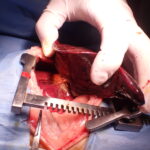

14歳のイタリアングレーハウンドが主訴として発咳を呈し、CT検査により左右両側の肺葉捻転が疑われた。肺葉捻転は稀であり、特に左右両側で発生することは極めて珍しい。左右肋間開胸術を実施して肺葉切除を行った。手術ではTA30Vステープラーを使用し、迅速かつ安全に肺葉切除が行われた。術後の経過は極めて良好であり、術後5日目には退院が可能となった。高齢犬でありながら、迅速な診断と適切な外科的介入が回復に寄与した。左右両側の肺葉捻転は非常に稀なケースであり、この症例は早期診断と外科的治療の重要性を示している。特にCTによる正確な診断と、適切な外科器具の使用が良好な術後経過につながった。肺葉捻転は自然発生的に、または乳び胸、外傷、腫瘍、慢性呼吸器疾患、あるいは過去の胸部外科手術などに伴って起こる。イヌの肺葉捻転は右中葉がもっとも多く(43%)、ついで左前葉に多く(35%)に起こることが報告されており、胸の深い犬種では右中葉に、小型犬種では左前葉に捻転が起こりやすいとされている。複数の肺葉に捻転が見られたことは稀である。